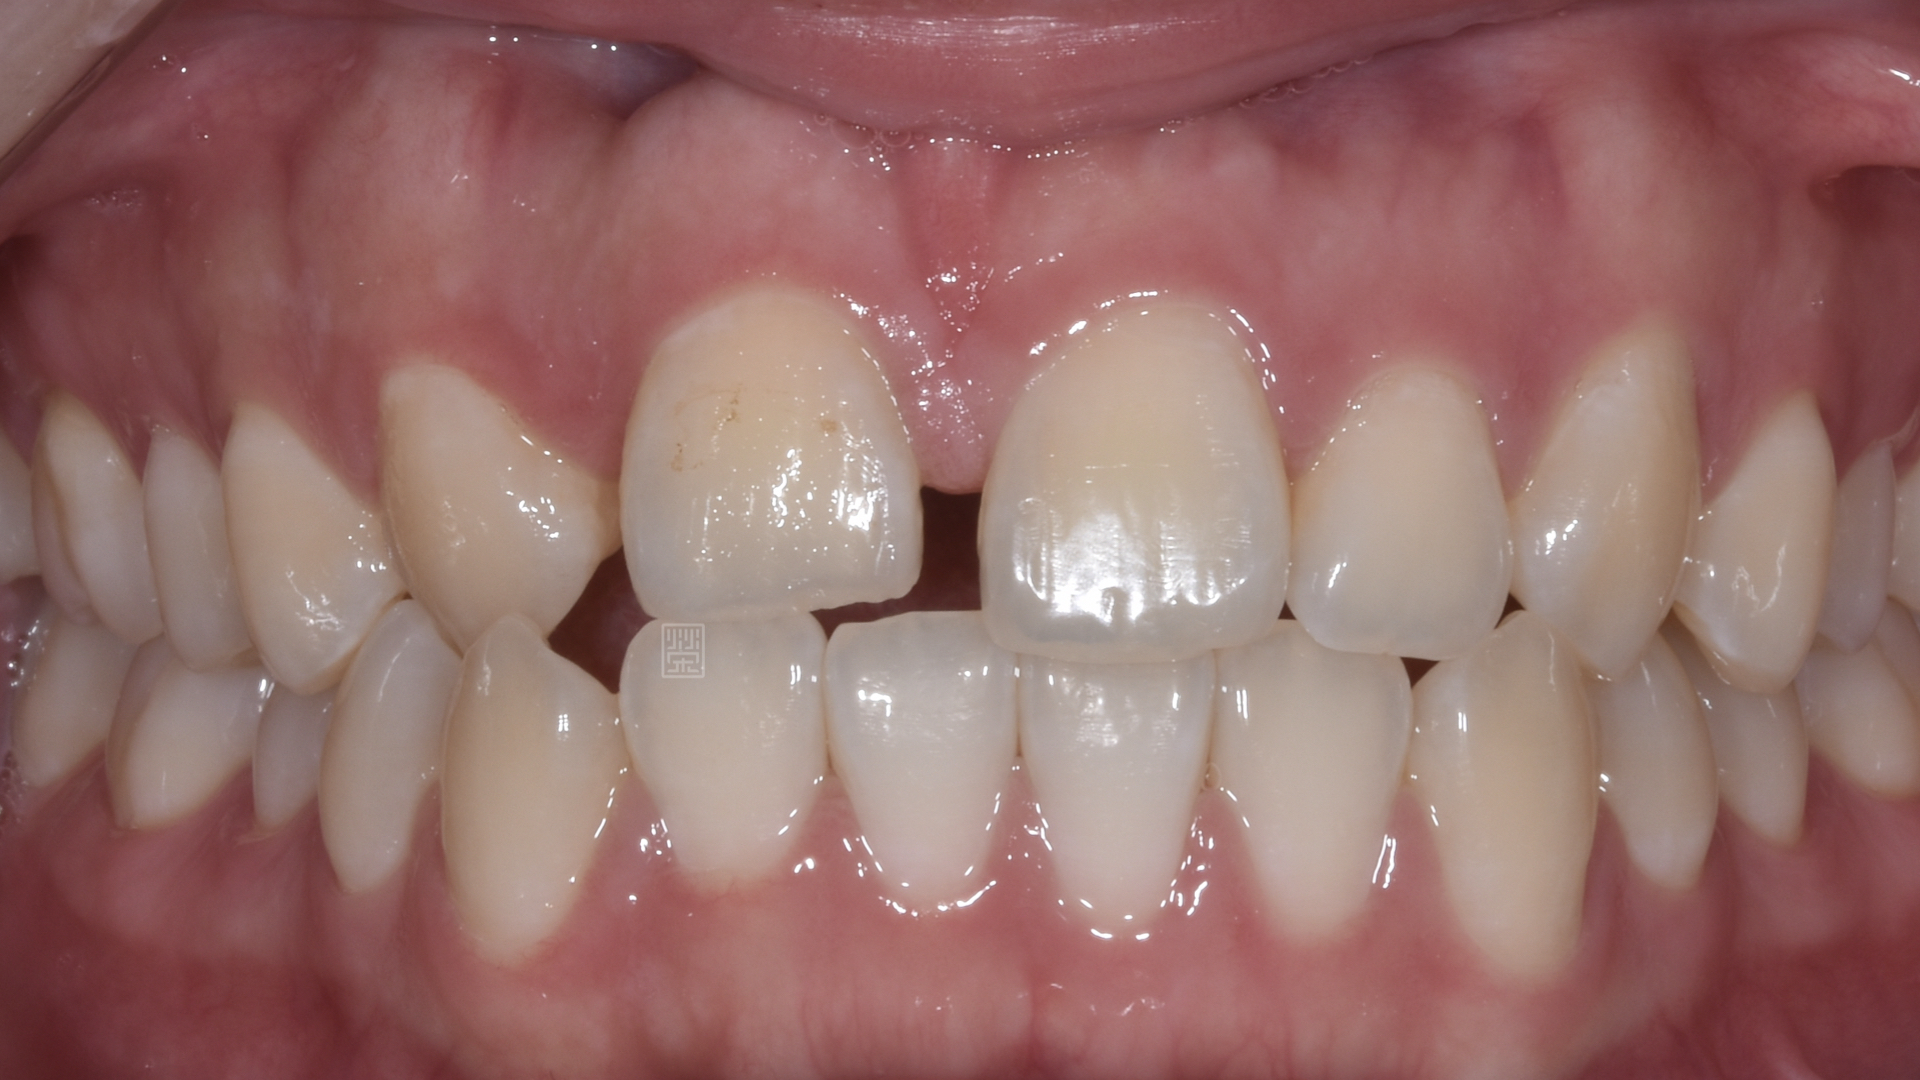

治療前牙齒因車禍有縫且缺牙

姚小姐在國中時因為車禍外傷,造成右側門牙位置撞偏,右側側門牙撞飛,之前也想過處理,諮詢過許多醫師,不是覺得太複雜,就是建議直接牙齒拔除都用植牙來處理。

由於門牙本身偏短,藉由微笑分析,決定由牙冠增長術與改變牙齒長度讓門牙達到更好的比例與對稱性,加上側門牙植牙牙齦的調整,並且將右側犬齒用全瓷冠恢復犬齒導引,達到保護性咬合,對未來咬合性穩定性更有幫助。